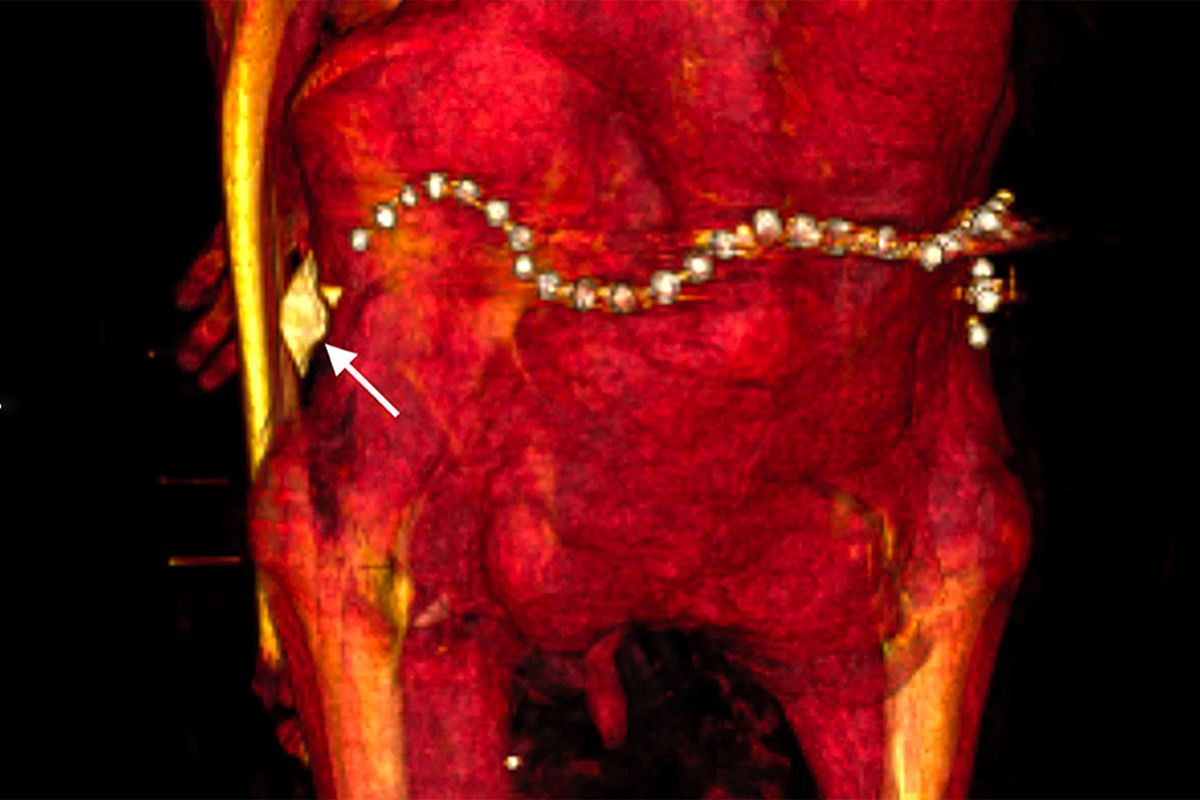

В бинтах исследователи также обнаружили около 30 украшений, в частности пояс из металлических (вероятно, золотых) бусин в задней части тазовой области, и фаянсовый амулет в форме раковины улитки у левого бедра.

Некоторые из украшений, вероятно, появились при повторном захоронении, считает Салим — так бальзамировщики хотели компенсировать ущерб, нанесенный грабителями.

Даже спустя несколько веков после смерти фараона древние египтяне все еще заботились о нем.